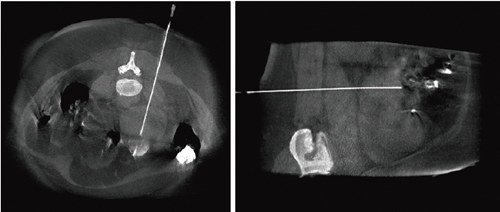

1.syngo iGuide Needleguidance

肺,腎臓,肝臓,骨髄など各臓器の診断に用いられる針生検や,肝臓の悪性腫瘍の治療法である経皮的ラジオ波焼灼術(RFA)などの穿刺ガイドを行う術中支援ツールが,この“syngo iGuide Needleguidance”である(図5)。穿刺部位の体表位置から目的臓器までの距離,穿刺部位からの直上視野角度とその直交する側面視野の角度をソフトウェアによって自動計算し,目的臓器までの穿刺を正確に支援する。また,LV DynaCTやDynaCT 360画像であれば,穿刺部位の体表と目的臓器の位置を,大柄な被検者でもその撮影視野を十分に確保することが可能となる。

図5 LV DynaCT画像による針生検の術中画像(画像提供:Siemens AG)